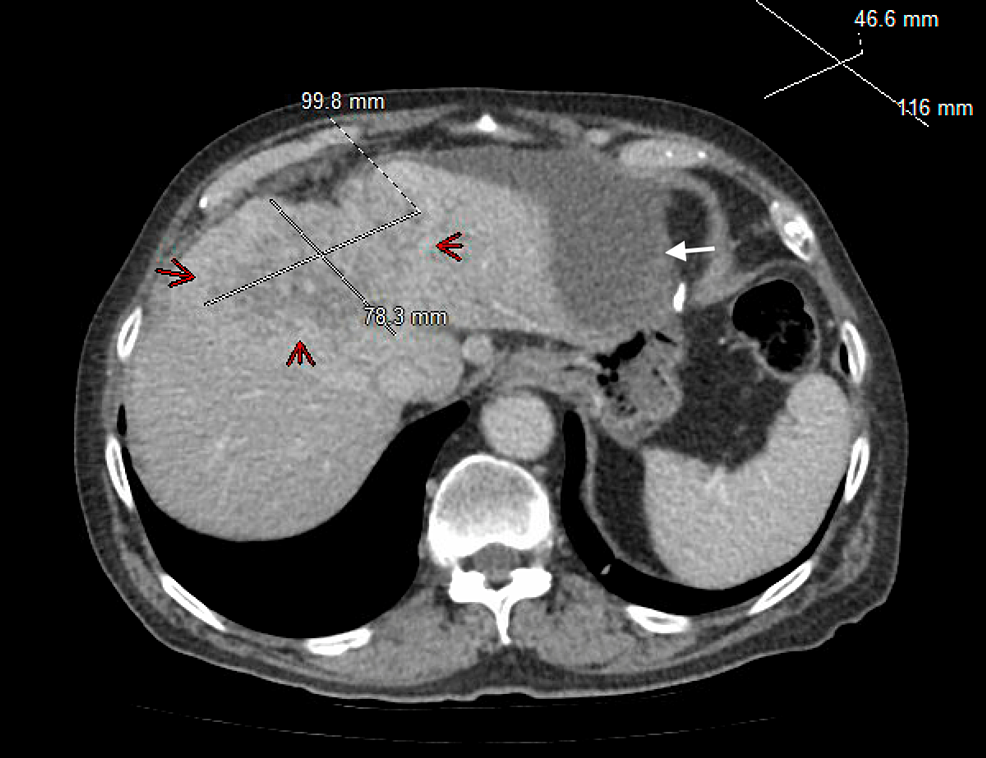

From www.researchgate.net

Abdominal CT (axial) demonstrated a large subcapsular biloma in the Radiology Biloma Bilomas, or extrabiliary collections of bile, have been reported to occur as a result of biliary surgery, endoscopic retrograde cholangiopancreatography (ercp) procedures, laparoscopic cholecystectomy [1], and trauma [2] and to occur spontaneously [3]. Biloma is a condition characterized by the collection of bile outside the bile ducts, often resulting from trauma, surgery, or liver. As clinical signs and symptoms of. Radiology Biloma.